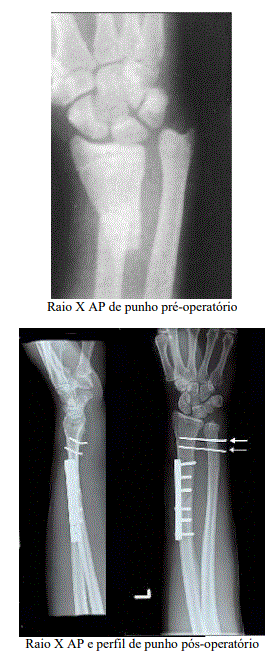

Uma paciente de 10 anos de idade, obesa, destra dominante,

sofreu queda de bicicleta com consequente trauma e fratura

do terço distal do rádio e luxação da articulação radioulnar

distal. Foi submetida à redução e fixação cruenta da fratura

para osteossíntese com placa e parafusos e fios de Kirschner,

conforme imagem. Ficou imobilizada por seis semanas com